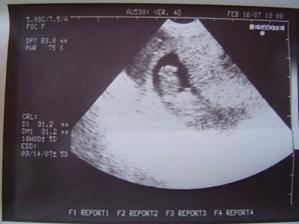

25. feb 2007

Nas pokladik Adamko

Asi presne na Vianoce 2006 sa nam podarilo stvorit maly zazrak, ktory bude snad pekne rast a robit nam radost 🙂

11.9. 2007 sa nam pokladik narodil a vola sa Adamko.